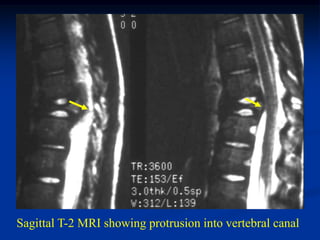

Case #438

7 year male with EG T-11

Sagittal gad contrast MRI

Sagittal T-2 MRI showing protrusion into vertebral canal